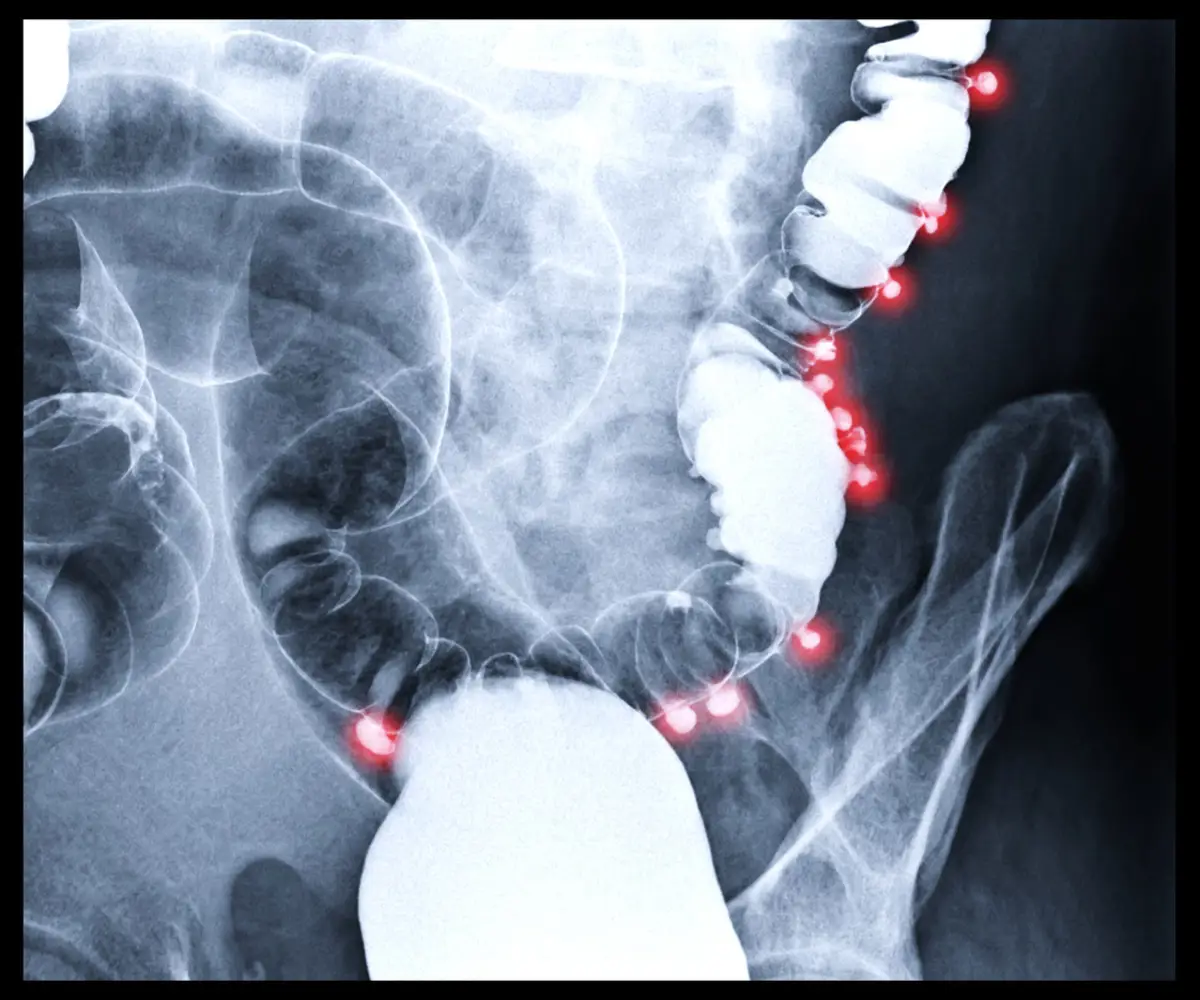

MADRID, 26 de marzo. (EUROPA PRESS) – La supervivencia en el cáncer de colon, que será el tumor más diagnosticado en 2026 en España, alcanza el 90 por ciento si se detecta de forma temprana, según la Fundación Española del Aparato Digestivo (FEAD).

Aun así, el especialista de la FEAD y médico adjunto en el servicio de aparato digestivo en el Hospital Universitario 12 de Octubre de Madrid, José Díaz-Tasende, ha asegurado que un test positivo no indica «por sí mismo» la presencia de un cáncer; esta condición solo se confirma en una minoría de personas, y es una señal de «la necesidad de realizar una colonoscopia». De hecho, en la mayoría de los casos se detectan durante este procedimiento pólipos o lesiones benignas que pueden predisponer al desarrollo del cáncer.

«La colonoscopia no solo permite un diagnóstico precoz, sino que también actúa como una herramienta preventiva, ya que durante la prueba se pueden extirpar estos pólipos y reducir así el riesgo de desarrollar cáncer en el futuro», ha recalcado el especialista.